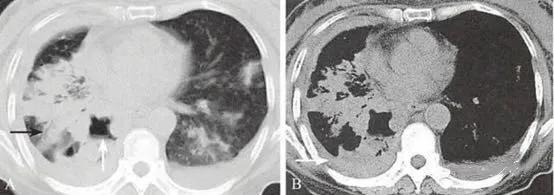

(3)弥漫型,肿瘤发生在细支气管或肺泡,弥漫分布于两肺。

两肺多发小结节或粟粒状结节,以中下肺为著,常伴有单侧或双侧的胸腔积液。结节大小不等,但每个结节的形态学表现与孤立性周围型肺癌具有相同的特征。